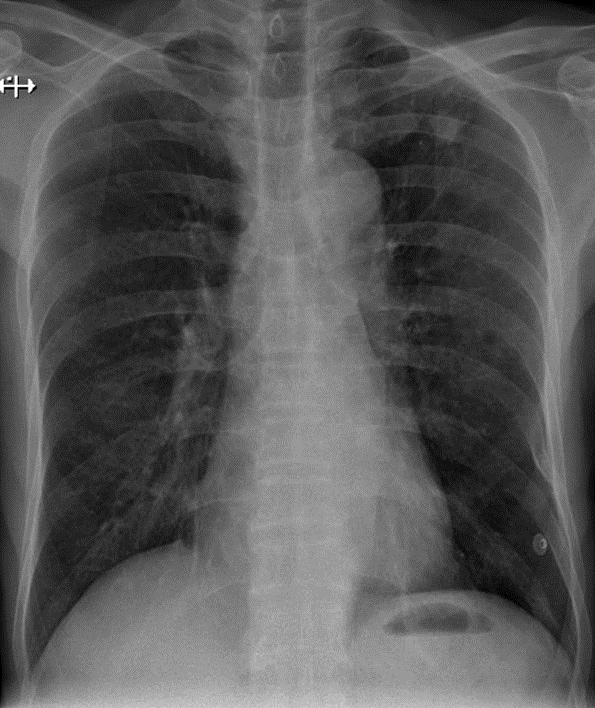

Hãy phân tích tình huống Nam 68 tuổi

1-Xơ vôi thùy trên phổi (T) 2-Gãy cũ cung sườn bên (T) số 8